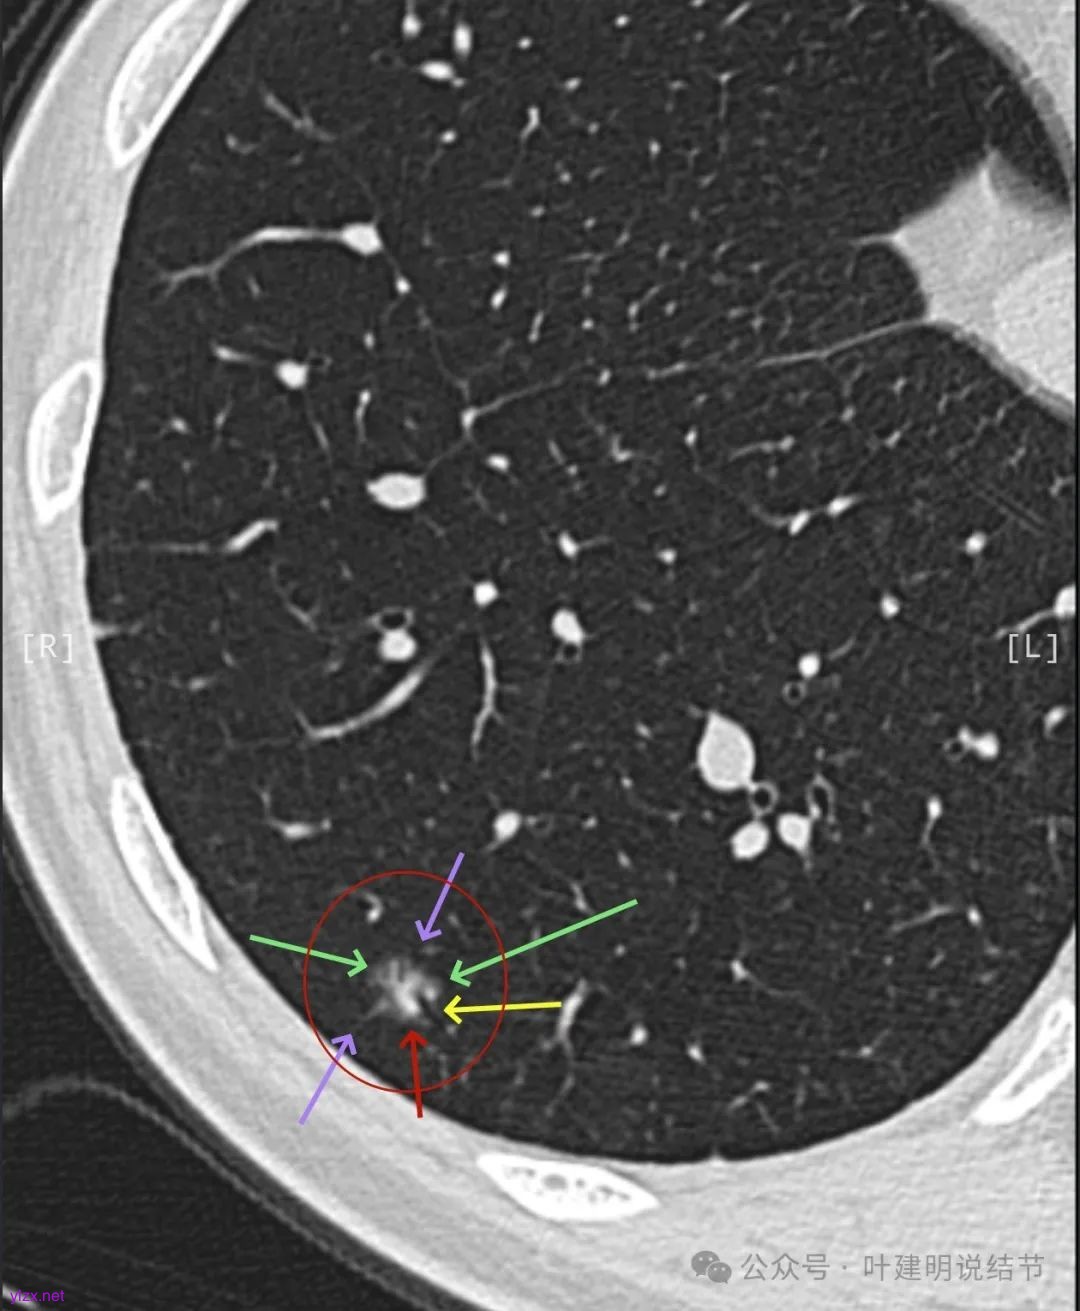

逐层看了2024年的影像:

我又建议其还是切了好。但嘱咐她不管病理是什么类型,只做楔形切除,因为毕竟7年才长这么点,浸润性癌也不会是恶性高会转移的亚型。

这个病例其实有反思回顾的价值,我想可以从中得出下面这些感想:1、混合磨玻璃结节随访持续存在且没有钙化或吸收好转,即使整体轮廓清,有血管征、有细支气管截断征、有毛刺与棘突征,且灶内密度杂乱,集齐许多恶性影像特征,仍不能下定论必为恶性;2、回头看病灶最终之所以不是恶性,而是慢性炎伴纤维增生与碳末沉积,最为关键的一是进展太慢,不符合混合密度结节含高密度实性成分的肺癌的生物学行为;二是实性部分密度过高而磨玻璃成分显得略偏模糊,看上去像有点晕征的味道。我反复总结过“混合密度实性成分过高而磨玻璃成分密度过低的容易是慢性炎或肉芽肿性炎伴纤维增生”。但临床的应用中仍不太敢下定论;3、多看几位医生也不能就100%明确。就如此例10位医生均考虑恶性范畴,虽有一位考虑原位癌,但其实也算是癌的范畴,但其实真正的影像上之所以判断的病灶部分不是肺癌,若牵强认为非典型增生与原位癌类似也可算浸润性病变,那也是碰巧而已,而不是从影像判断上看出有不典型增生,而密度高的却认定是良性成分;4、手术切除与否对于此例来说,仍是值得的,因为问了10位医生都说是肺癌,即使随访也压力巨大,而且密度不纯。从结果来看,已经存在非典型增生,继续随访,多年后也可能还是会发展成微浸润性腺癌或浸润性癌的可能性。而且楔切创伤不大,既明确诊断,也去除了病灶,是利大于弊的。当然这再次印证我一直坚持的原则:从风险高低来考虑手术与否以及干预的时机,而不要过于在意最后的病理结果。